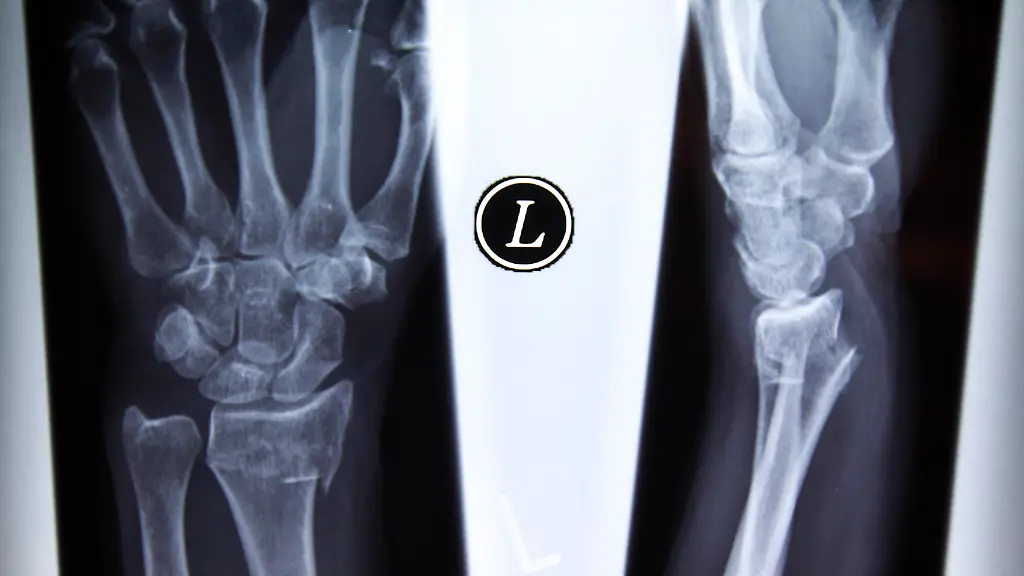

Die Gefahr von Brüchen im Alter wird durch Sport in der Jugend geringer.

(Foto: REUTERS)